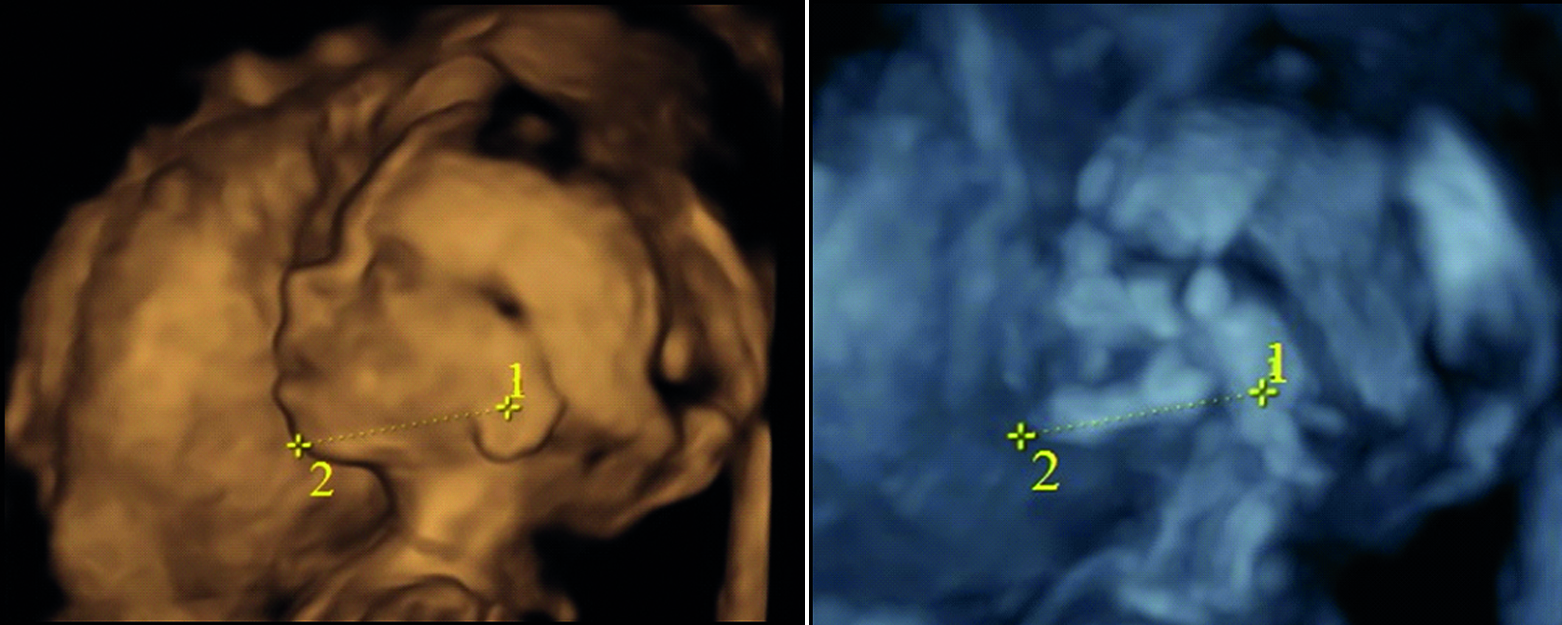

Методом ультразвукового сканирования можно изучить топографию, форму, структуры ушной раковины плода [13]. В исследовании использовались два режима: поверхностной реконструкции и костный (рисунок 1). Во всех случаях определяется условный центр ушной раковины. В костном режиме отчетливо визуализируются костные структуры, в режиме поверхностной реконструкции можно оценить форму ушной раковины и детали строения: завиток, противозавиток, козелок, противокозелок, мочку уха. Форма ушной раковины у плодов вариабельна (таблица 1).

Примечание. 1 – центральная часть ушной раковины; 2 – гнатион.

Рисунок 1. Ультразвуковая сканограмма головы плода. Возраст 20 недель, пол мужской. А – режим поверхностной реконструкции; Б – режим скелетный.

Figure 1. An ultrasound scan of the fetal head. 20 weeks old, male. A – a surface reconstruction mode; B – a skeletal mode.